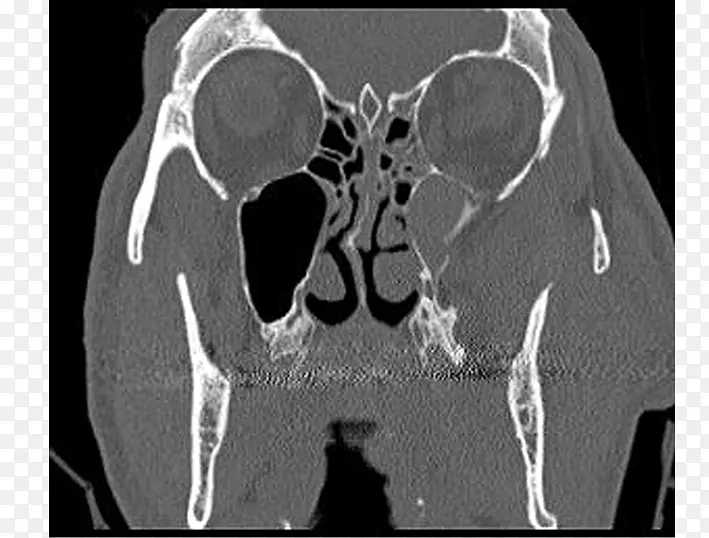

l ketieteellinen r ntgenkuvaus骨X线摄影-骨折-图片素材分享-空若网